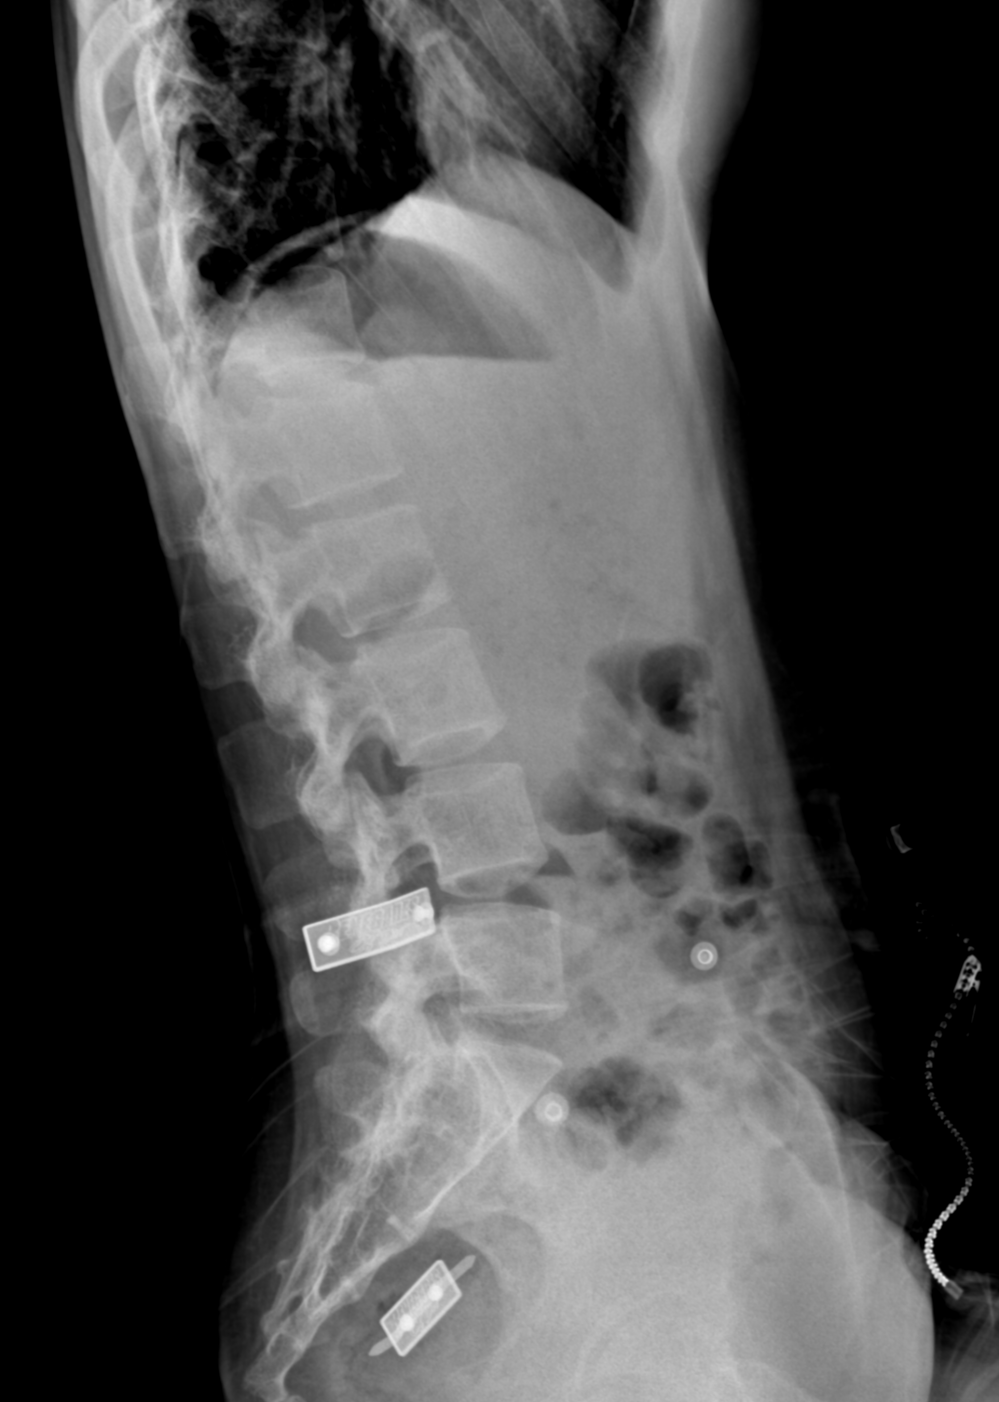

Gần đây, cột sống của cô gái cong lên bất thường.

Càng ngày, tình trạng của Vân ngày một nghiêm trọng hơn. 27 tuổi, người cô nghiêng hẳn về một bên khi đứng. Phần cột sống thắt lưng cũng cong lên bất thường, kèm theo đó là triệu chứng đau mỏi lưng, ảnh hưởng không ít đến việc học tập và sinh hoạt của Vân. Cô như rơi vào bi kịch không lối thoát.

Từ đông y đến tây y, từ bệnh viện này đến phòng khám khác Vân đều đã thử qua nhưng không mấy khả quan. Có nơi còn chỉ định cho cô gái mổ chỉnh hình cột sống với lời khuyến cáo rủi ro sẽ cao.